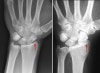

X-ray : 손목 관절염(Wrist arthritis)